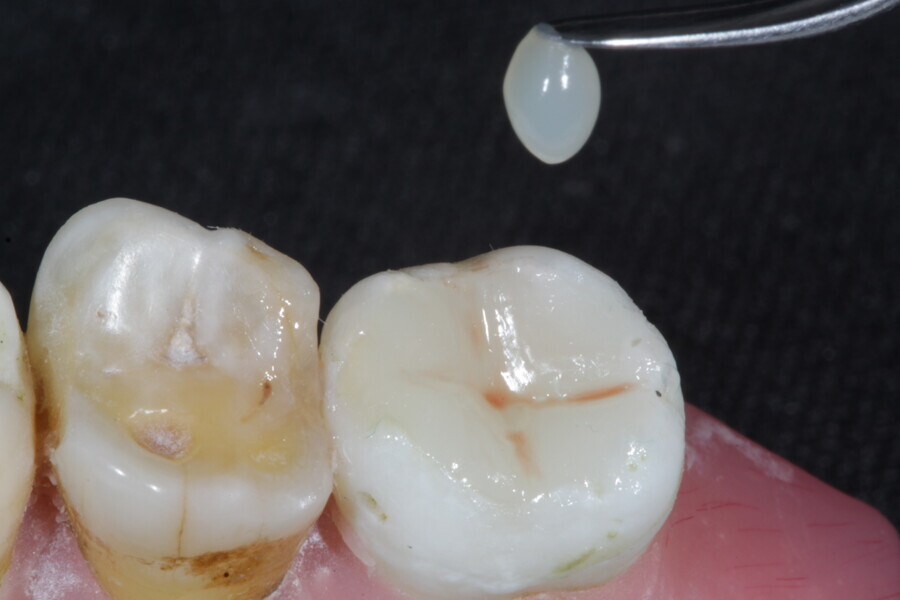

The second step focuses on reinforcing the restoration through careful fibre and FRC selection and placement. Tooth preparation should involve minimal removal of tooth structure to preserve as much natural tooth as possible in preparing the cavity for the restoration. Fibres or layers of FRC (flowable, paste, cube, etc.) are then strategically placed within the prepared tooth and composite material to reinforce areas susceptible to high stress and occlusal forces based on occlusal contact mapping. This strategic selection and placement of fibres and layers of FRC is crucial for enhancing the strength and longevity of the restoration.

1. direct restoration using a fibre-reinforced flowable composite and membrane cube after endodontic treatment (Figs. 21–35); and

1. restoration reinforcement of a vital tooth with a fibre-reinforced flowable composite and membrane (Figs. 36–45).